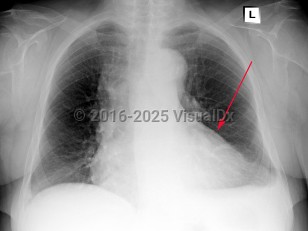

Symptoms and Signs: Acute pericarditis typically presents with sharp pleuritic chest pain, exacerbated by the supine position and improved with leaning forward. Fever and myalgias may be present but are not required features. On examination, a scratch-like friction rub (pericardial rub) may be heard, although this is present in less than 33% of cases. To make the diagnosis of pericarditis, the patient must have 2 of 4 criteria: pericardial rub, chest pain, ECG changes, and/or presence of a pericardial effusion. Chest pain has the highest incidence and is seen in 85%-90% of cases.

While not usually life-threatening, acute pericarditis can progress to cardiac tamponade or constrictive pericarditis in some complicated cases. Consider constrictive pericarditis in cases of unexplained heart failure. Tricuspid regurgitation is common in these patients and is associated with increased mortality. Other findings in constrictive pericarditis can include Kussmaul sign (a paradoxical increase in jugular venous pressure on inspiration), jugular venous distention, peripheral edema, hepatomegaly, and pericardial knock.